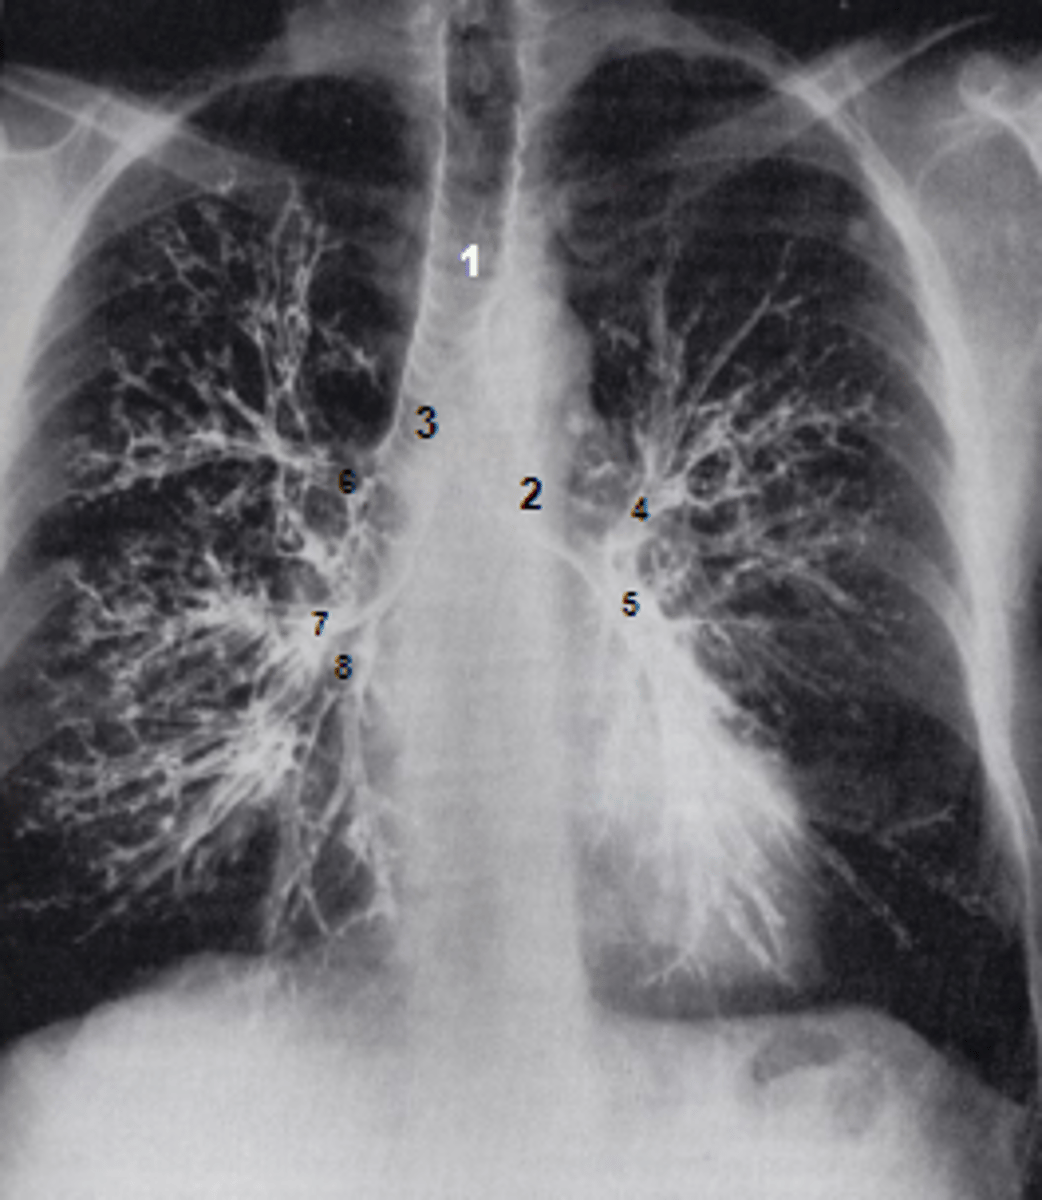

1

at what number is the arch of aorta?

2

at what number is the superior vena cava

3

at what number is the right atrium

4

at what number is the left ventricle

5

at what number is the primary bronchus

6

at what number is the dome of diaphragm

7

at what number is the first rib

8

at what number is the clavicle

9

at what number is the acromion of scapula

10

at what number is the coracoid process of scapula

11

at what number is the transverse process of vertebra

12

at what number is the spinous process of vertebra

1

at what number is the trachea

2

at what number is the left main bronchus

3

at what number is the right main bronchus

4

at what number is the left superior lobar bronchus

5

at what number is the left inferior lobar bronchus

6

at what number is the right superior lobar bronchus

7

at what number is the right middle lobar bronchus

8

at what number is the right inferior lobar bronchus